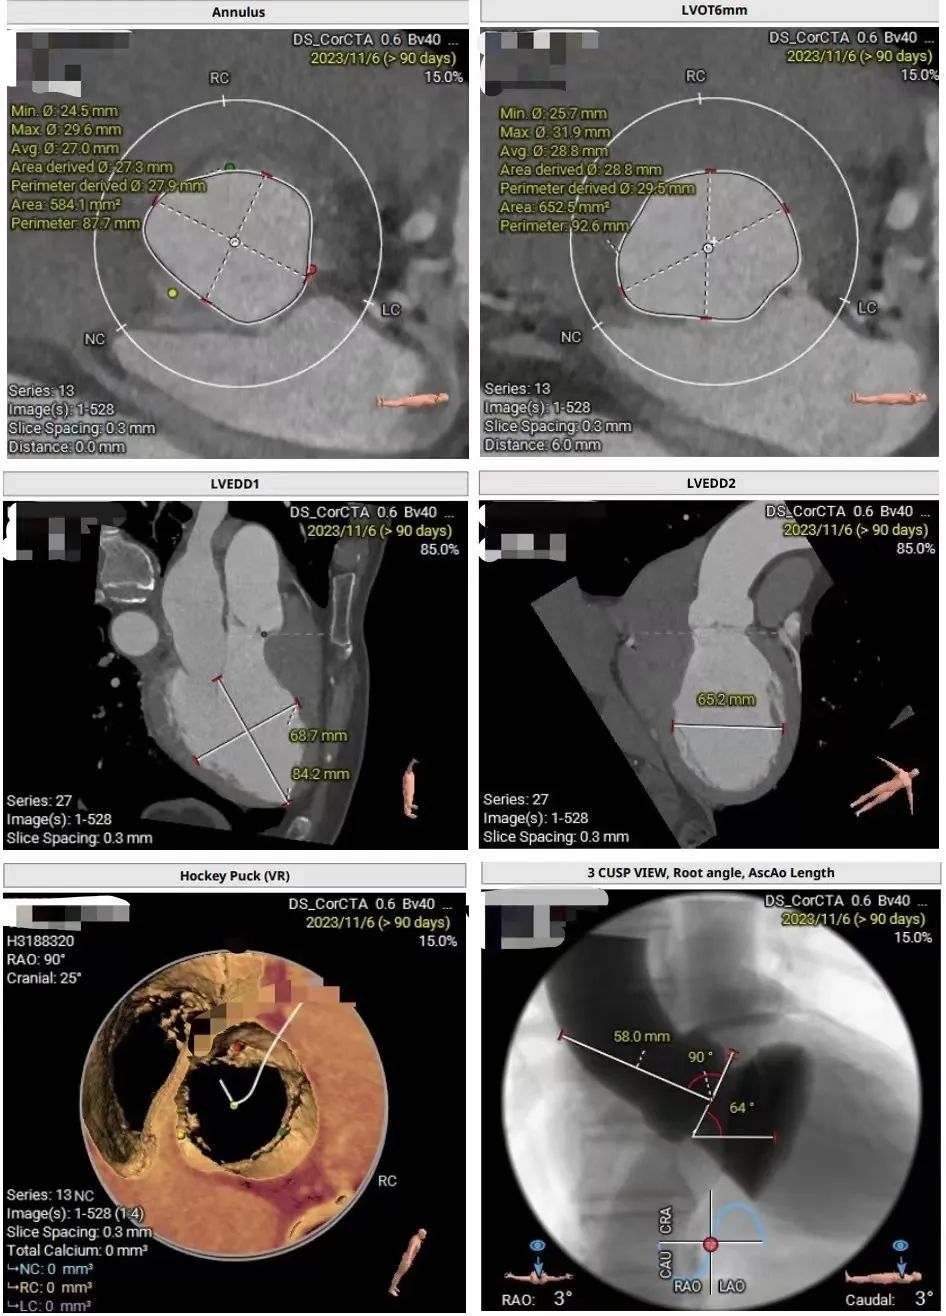

术前CT评估显示,瓣环周长为87.7mm (oversize: 7.5%),LVOT 92.6cm(oversize: 9.9%),呈敞口型。VR相显示主动脉根部无钙化。瓣环水平夹角64°。外周入路条件良好,术前策略讨论拟使用右窦中心位进行瓣膜定位及释放。